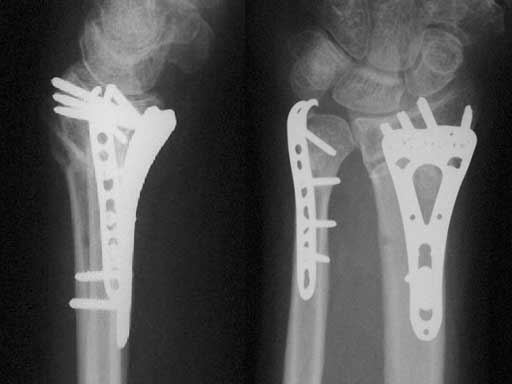

A 48-year-old female had an accident while on vacation. Local temporary treatment was performed with a bridging external fixator and definitive treatment with a plate 2 weeks postinjury.

Fig 2ab AP and lateral x-rays 4 months after ORIF of a segmental unstable fracture of the distal ulna including basistyloid avulsion and extraarticular fracture of the distal radius.